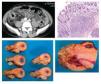

Antecedentes: El síndrome de Alagille es un trastorno multisistémico de herencia autosómica dominante que afecta al hígado, corazón, ojos, cara, sistema óseo y otros sistemas. Las manifestaciones clínicas son diversas, desde casos subclínicos hasta grados graves con insuficiencia hepática y malformaciones cardiacas complejas. El diagnóstico se ha basado por lo regular en el hallazgo de escasez de conductos inter-lobulillares (91% de los casos), relacionada con al menos tres de los cinco criterios mayores: colestasis (94%), malformaciones cardiacas (92%), facies característica (91%), anomalías oculares (80%) y anomalías vertebrales (67%). Existen muy pocos casos publicados en la bibliografía mundial sobre la presencia de hepatocarcinoma en la edad adulta, y menos aún en la edad pediátrica, con tan sólo menos de 10 casos reportados, por lo que en la mayor parte de las ocasiones se trata exclusivamente de informes de casos.

Material y métodos: Se realizó la revisión del expediente clínico de un paciente con síndrome de Alagille.

Resultados: Paciente con síndrome colestásico, diagnosticado con síndrome de Alagille; entre los criterios mayores que el enfermo presentaba figuraban colestasis, malformaciones cardiacas (estenosis periférica de la arteria pulmonar), facies característica, anomalías oculares (embriotoxón posterior) y anomalías vertebrales (hemivértebras). Se realizaron USG hepáticos múltiples entre los dos meses y el año de vida, con hepatomegalia y hepatopatía difusa. La angiotomografía al año de edad fue normal, sin lesiones parenquimatosas; el USG y la biopsia hepática al año siete meses mostraron cirrosis biliar micronodular, espacios porta con fibrosis e inflamación crónica leve, proliferación y destrucción de conductos biliares, colestasis intracelular y extracelular, sin masas en el parénquima hepático. Tuvo seguimientos mensuales, sin deterioro en la exploración física o cambios en laboratorios. Un nuevo USG a la edad de dos años seis meses mostró neoformaciones sólidas vasculares, en el lóbulo hepático derecho, y esplenomegalia. TAC con presencia de neoplasia hepática y metástasis pulmonares. Biopsia con hepatocarcinoma de patrón acinar, parénquima hepático con nódulos de regeneración ductopénica y fibrosis perisinusoidal acentuada. Inmunohistoquímica: fetoproteína a (+), ck7 y ck20 negativas y k167 positiva en 70% de las células neoplásicas. Fetoproteína a, 2 031 507. Por el estado avanzado de la neoplasia el paciente falleció a los tres meses posteriores al diagnóstico a la edad de dos años ocho meses.

Conclusiones: El pronóstico depende de la gravedad de la enfermedad hepática. En la mayoría de los casos la supervivencia es de 50% a 85% en la etapa adulta y 10% a 50% desarrolla insuficiencia hepática, cirrosis e hipertensión porta, resistente al tratamiento. Hasta 20% a 31% requiere trasplante hepático. Sin embargo, se ha documentado la presencia de hepatocarcinoma a temprana edad, de lo cual se dispone de escasa información, tanto en la edad adulta como en la pediátrica; este paciente es probablemente el caso diagnosticado a edad más temprana. Se debe tomar en cuenta la posibilidad de presentación de una neoplasia para un seguimiento aún más estrecho con estudios de imagen en este tipo de individuos.